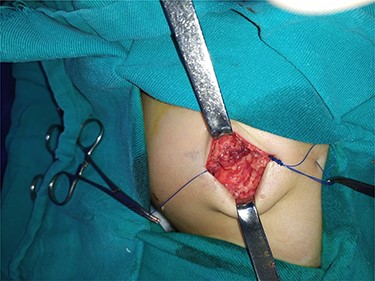

After studying the case, we decided to perform primary repair of the abdominal wall defect without meshplasty since the diameter of the aperture was <5 cm. An oblique left lumbar incision was performed above the hernia, revealing a defect measuring 4 cm in diameter in the upper lumbar triangle. Dissection of the peritoneum and hernial sac was performed starting from the margins of abdominal muscles (Fig. 4), the hernial sac was internally reduced and the muscular margins were closed by simple continuous sutures made from prolene 0 (Fig. 5). Complete closure of the defect was confirmed and a draining tube was inserted subcutaneously before closing the skin. The drain was removed after 2 days; the stitches were removed after 10 days. The patient was faring well after the surgery. Recurrence of the hernia was not reported. We recommended that the patient should be followed up by an orthopedist for the correction of disability, which is caused by LCVS.